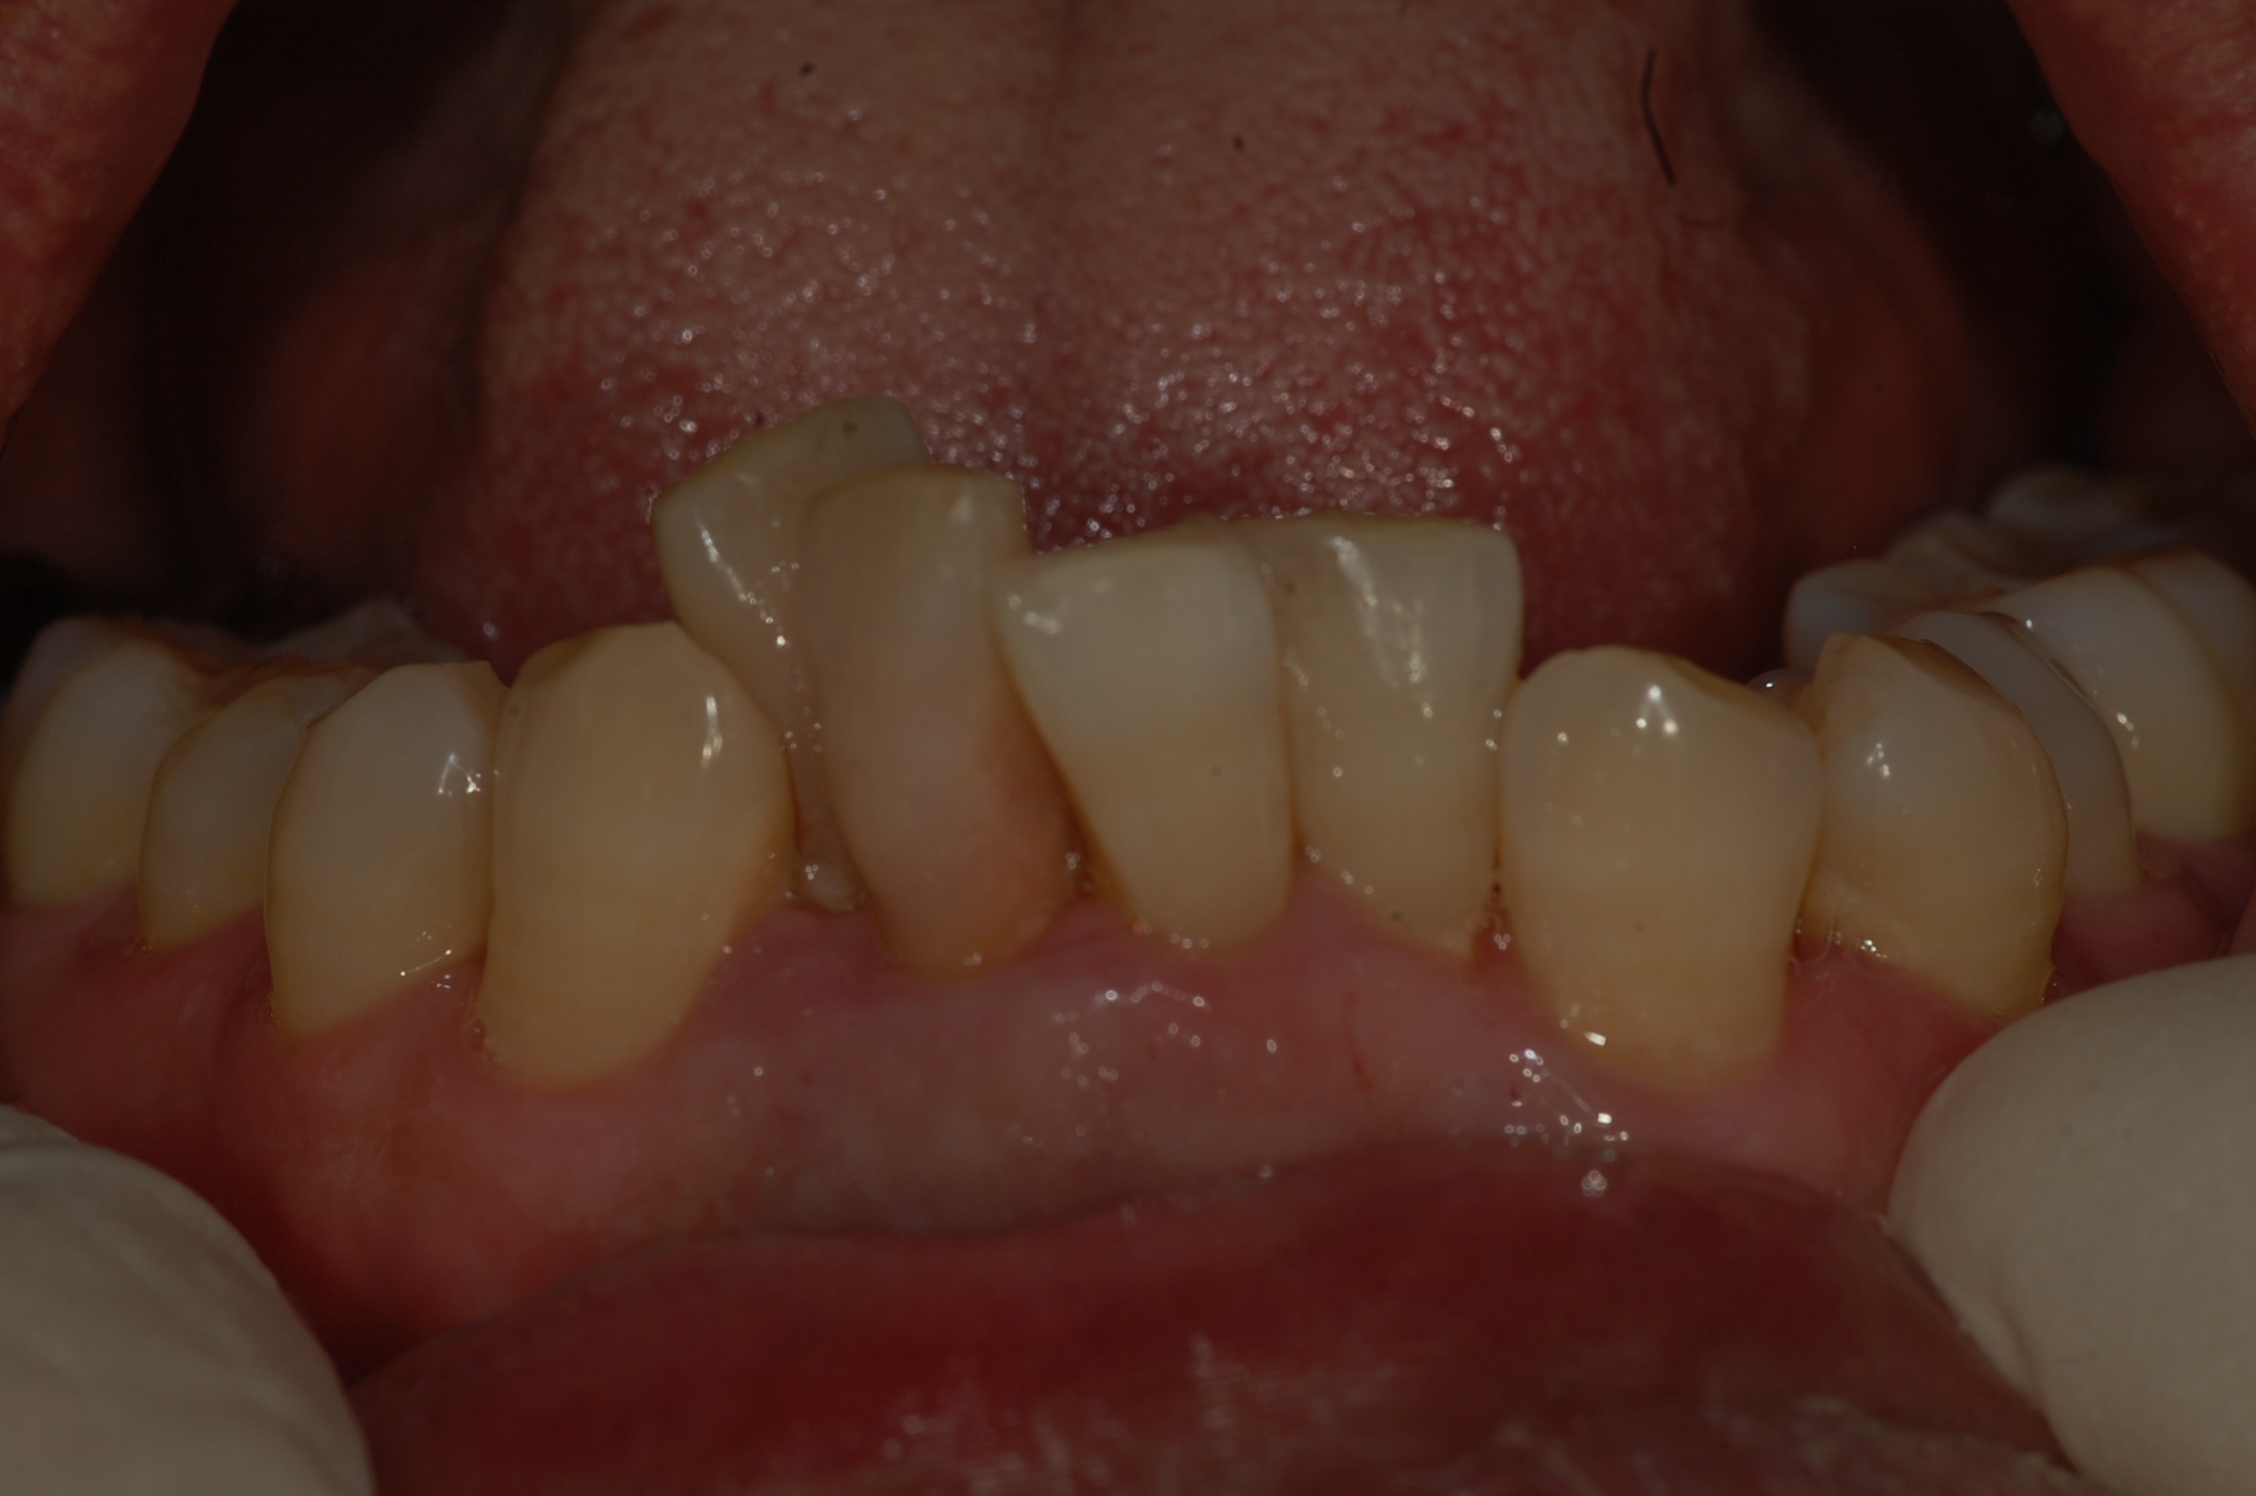

[임플란트] 제목 : 아래 앞니 임플란트

치주질환으로 발치 후 치료